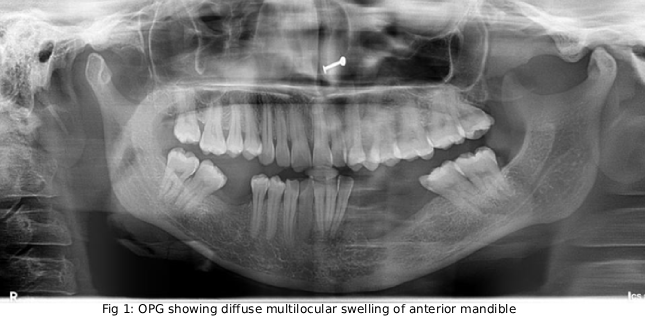

Case Study 1

Final Diagnosis: Fibrous Dysplasia Of Maxilla